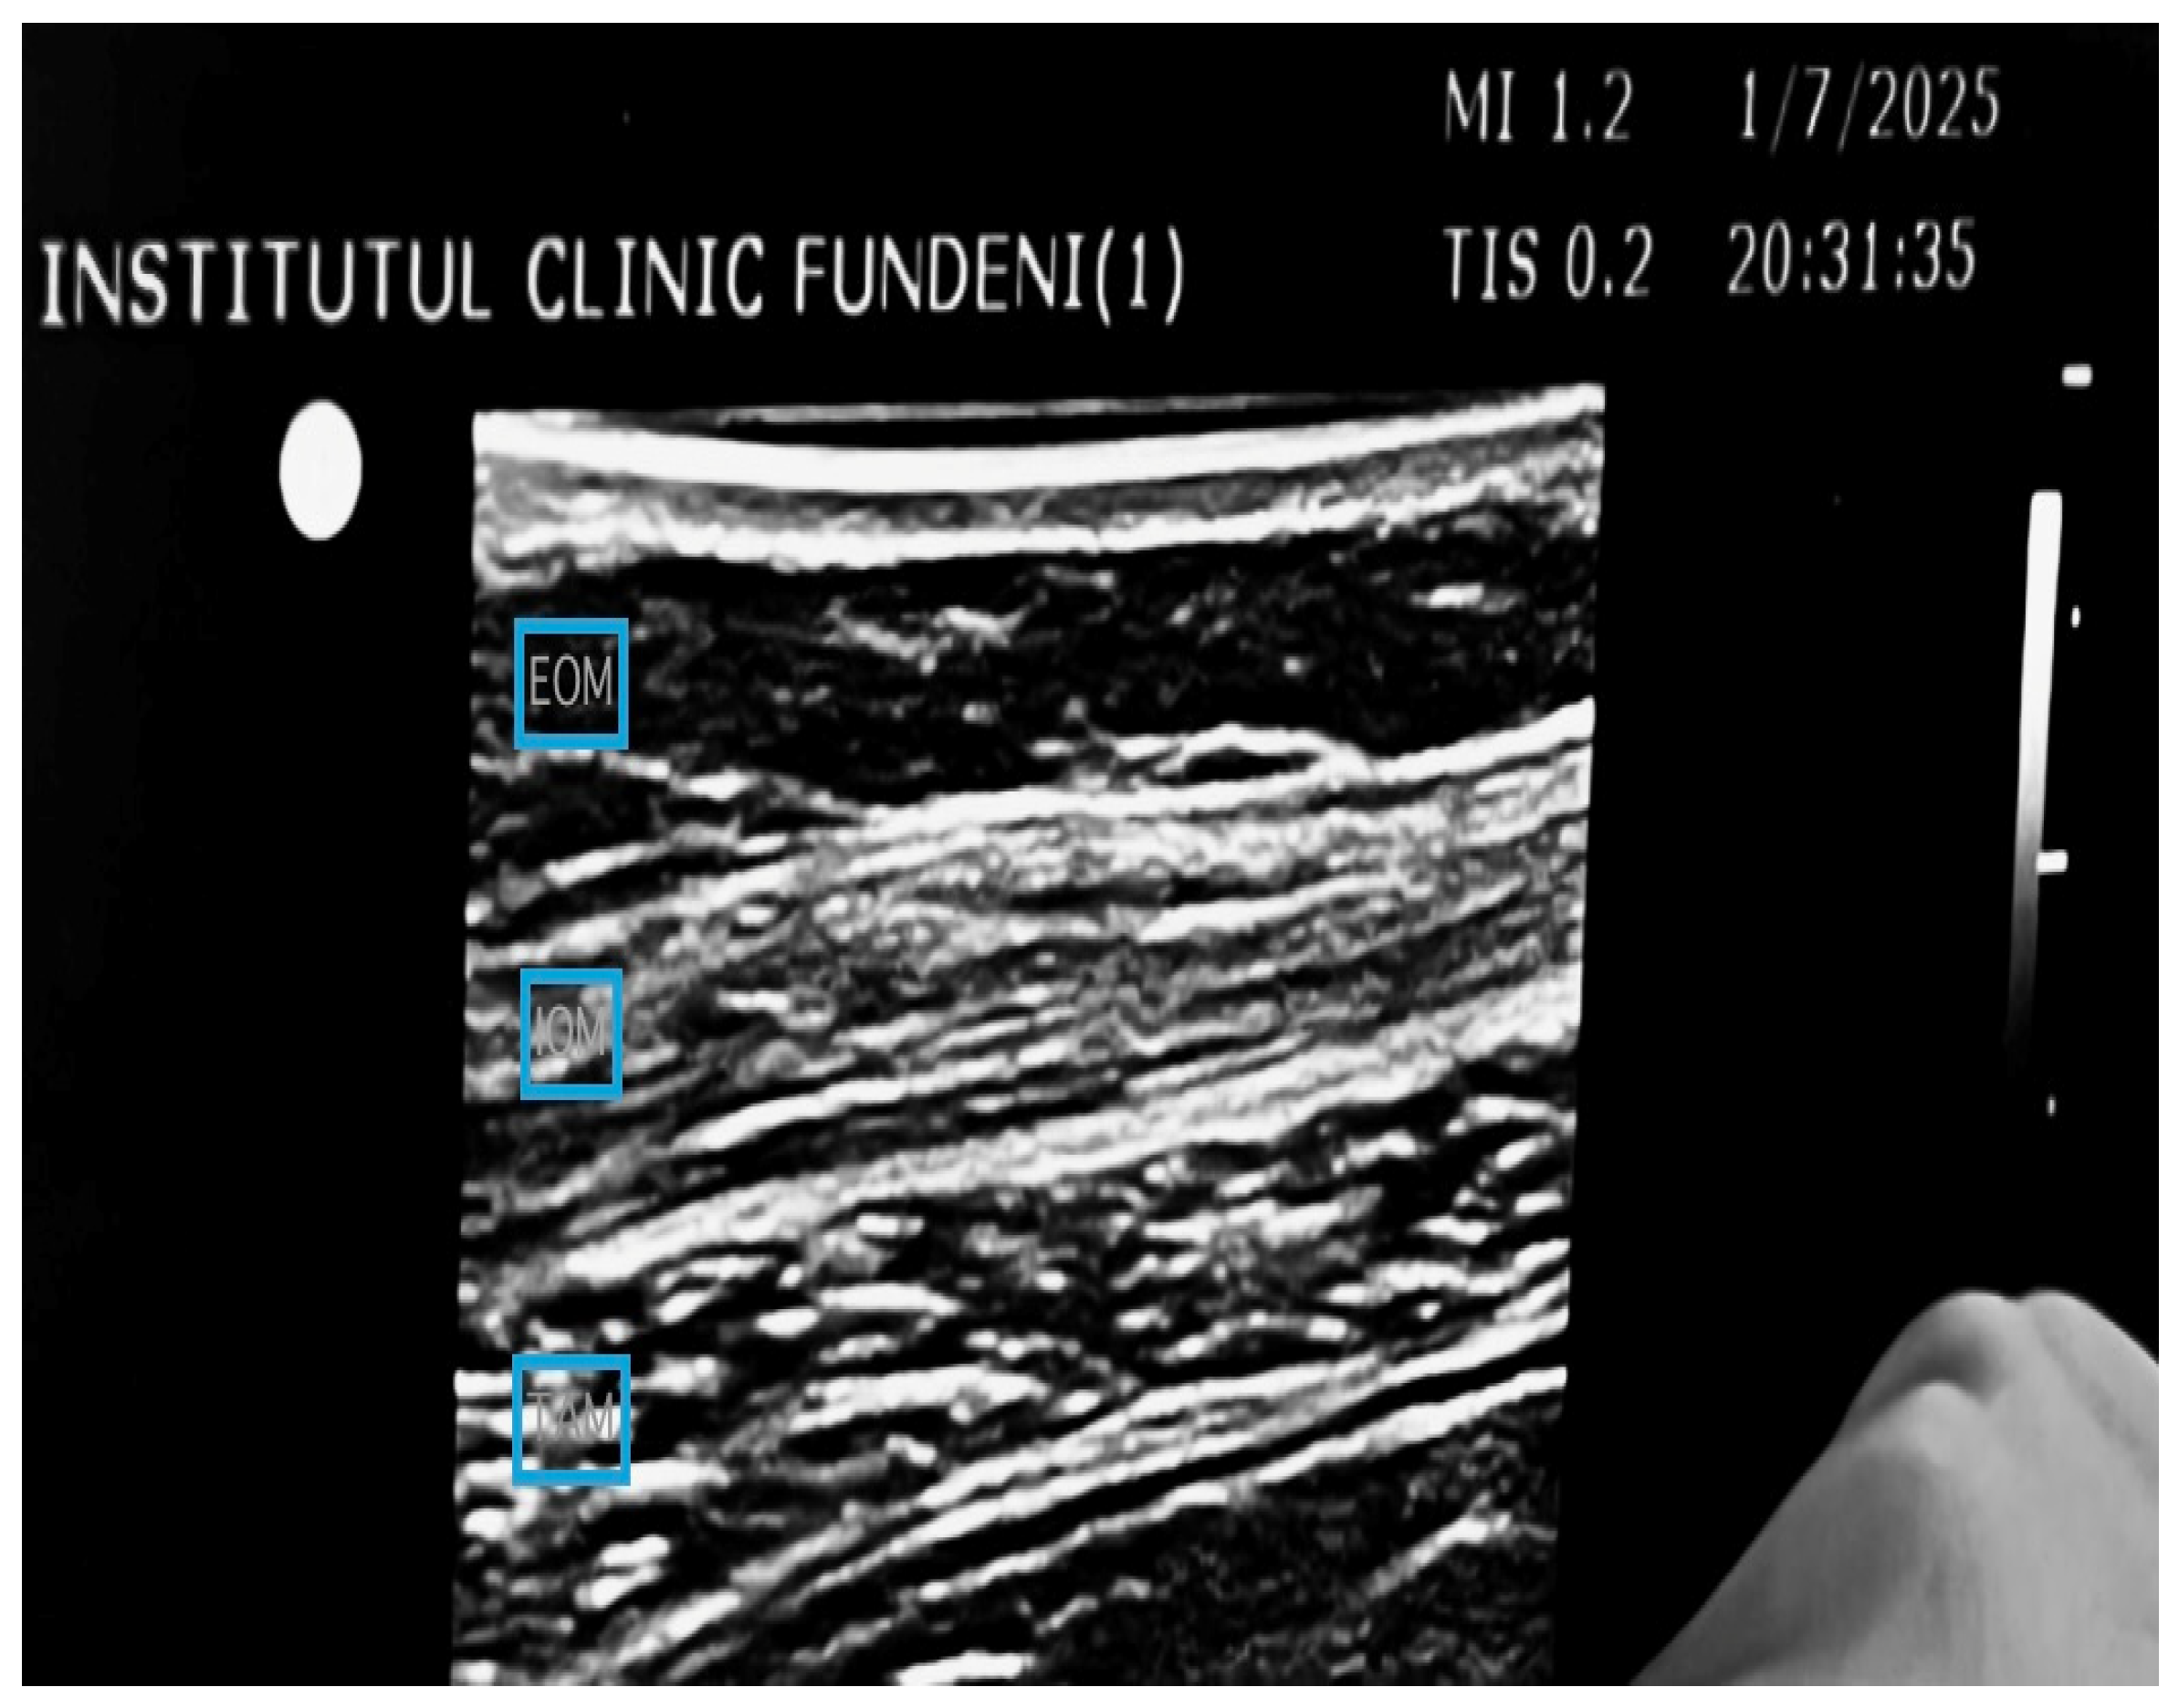

2.4.2. Group TAP (n = 54)